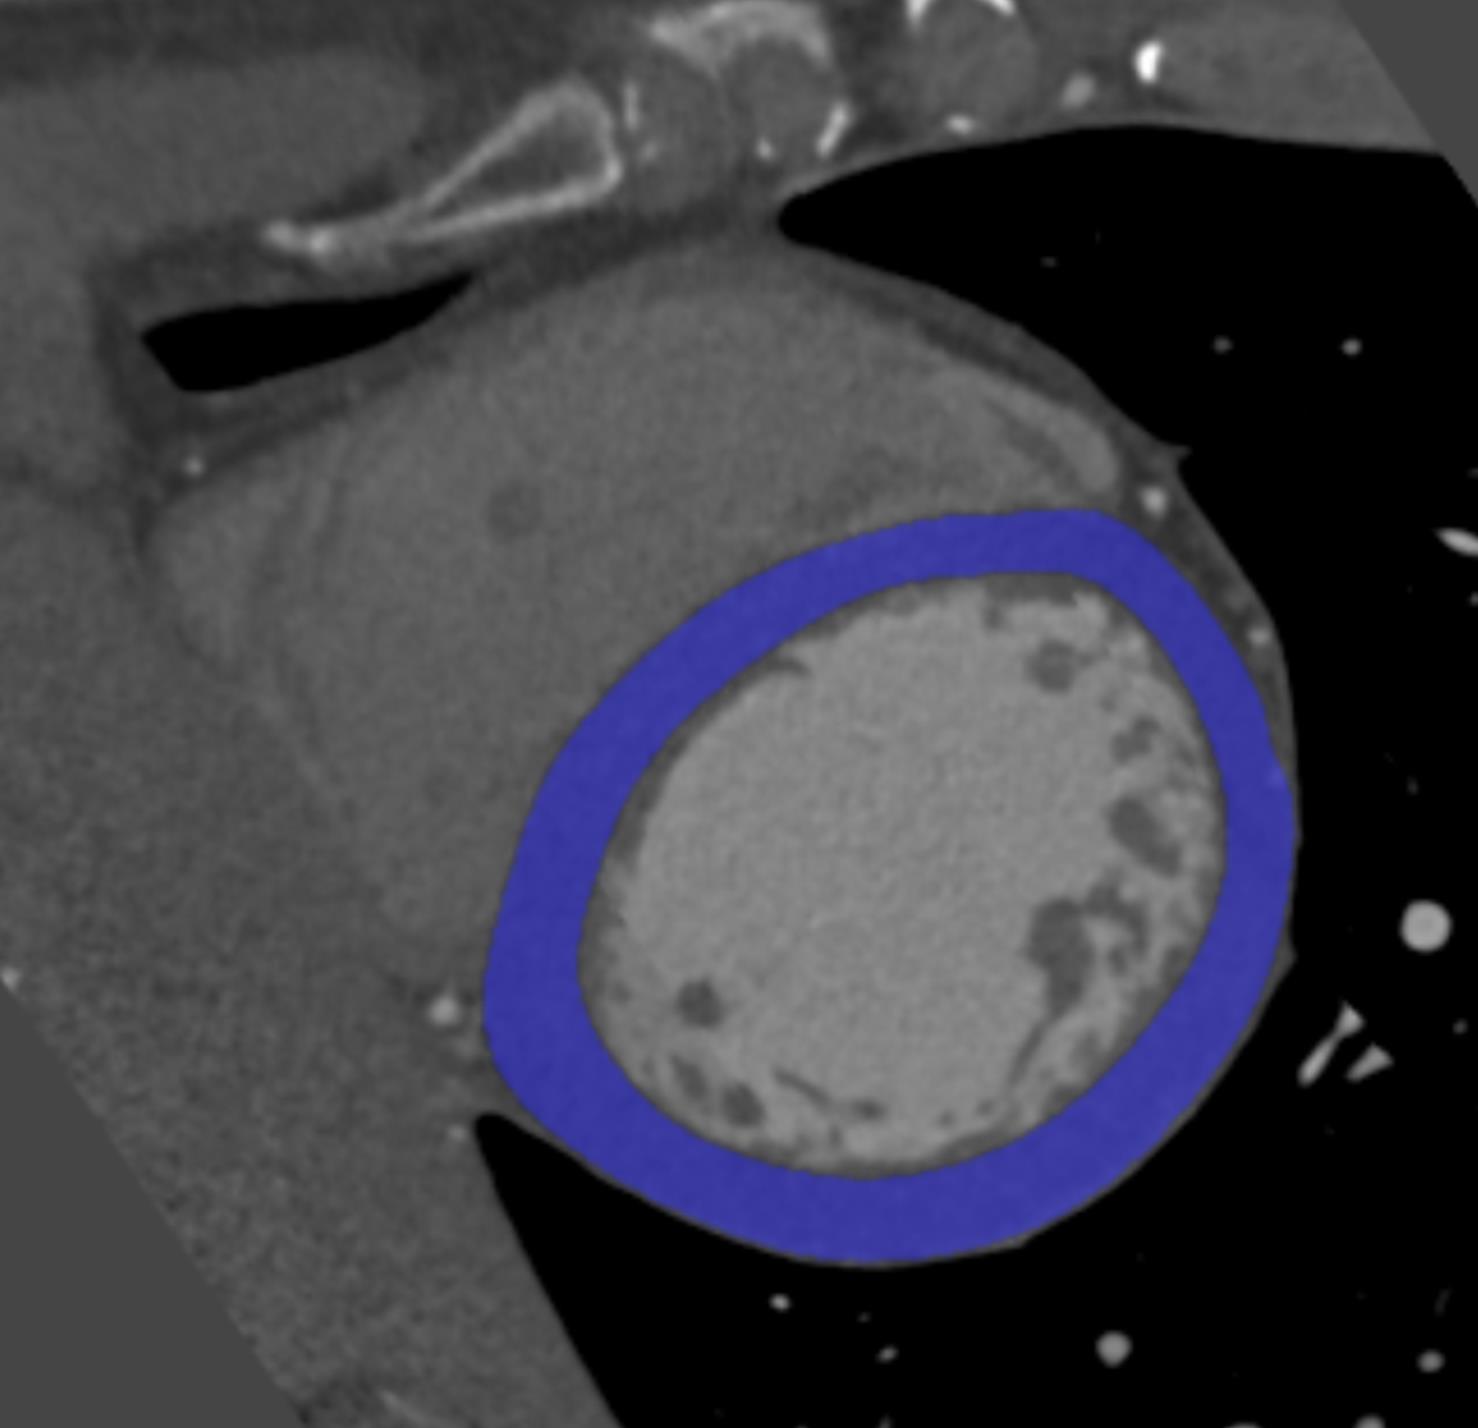

To train, validate and test the segmentation of LV myocardium, the myocardium was manually annotated in 40 randomly selected CCTA scans. Manual annotations were performed by a trained observer using custom-built software created with the MeVisLab111http://www.mevislab.de platform. Following clinical workflow, annotations were performed in the short axis view of the heart, while excluding myocardial fat, papillary muscles and the trabeculae carneae. Segmentation was performed by manually placing points along the endocardium and epicardium in every third image slice. From the defined points, closed contours for the endocardium and the epicardium were created by cubic spline interpolation. The contours were propagated to the adjacent slices where they were manually adjusted when needed by moving existing or placing new points. Reference LV myocardium contained all voxels enclosed by the manually annotated endocardial and epicardial contours. Fig. 3 illustrates a typical short axis view of the LV myocardium and the annotated manual reference.

Manual annotation of the LV myocardium is a time-consuming task. Therefore, automatic segmentation was evaluated quantitatively in a subset of test scans with manually defined reference and qualitatively in all test scans.

Quantitative evaluation was performed using the Dice coefficient, as an overlap measure between reference and automatically segmented volumes. In addition, the mean absolute surface distance (MAD) between the reference and automatically segmented LV boundaries was computed.

Qualitative evaluation was performed by an expert who visually inspected and graded the automatic segmentation using the quality grades as defined by Abadi et al. [2010].

Fig. 8 illustrates segmentation results. Quantitative evaluation of the segmentation performed on the 20 test scans resulted in a Dice coefficient of and a MAD of mm. Qualitative evaluation of the segmentation was performed in all 146 test scans. Results are summarized in Table 2.